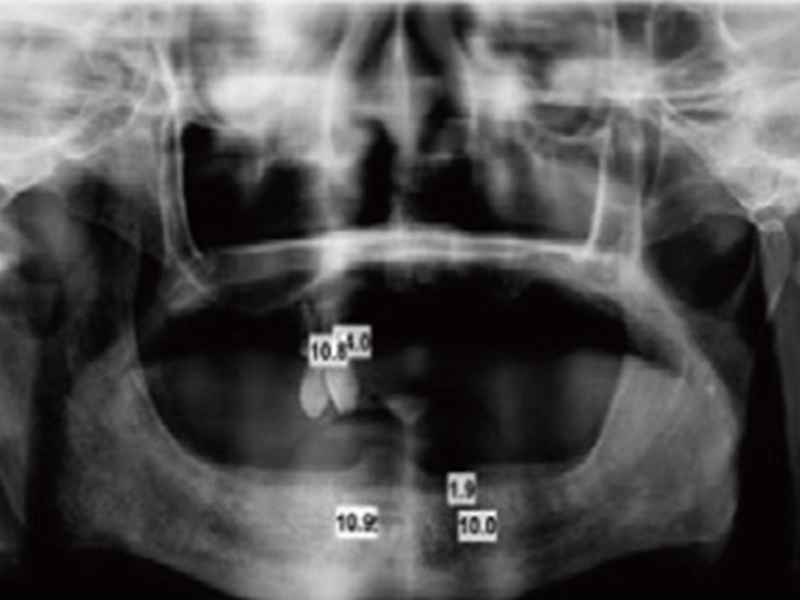

1. Take X-ray

Take X-ray and decidethe placement location for the dental implants.